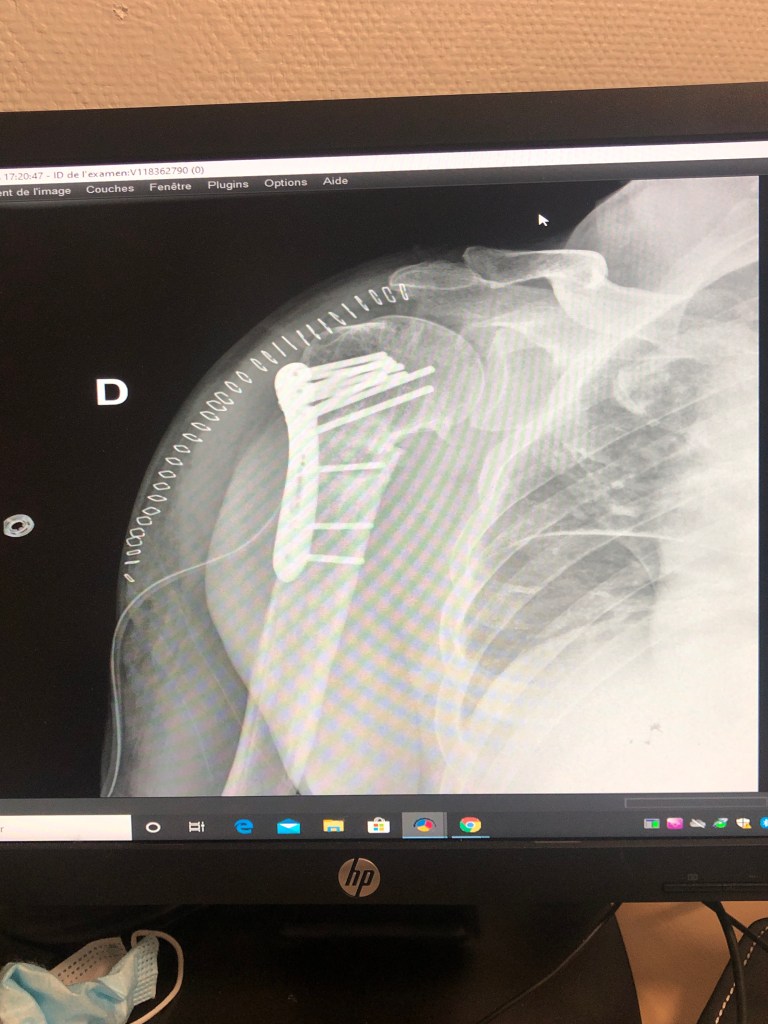

Vous trouverez ci après les interventions réalisées par le Dr DOLEAC